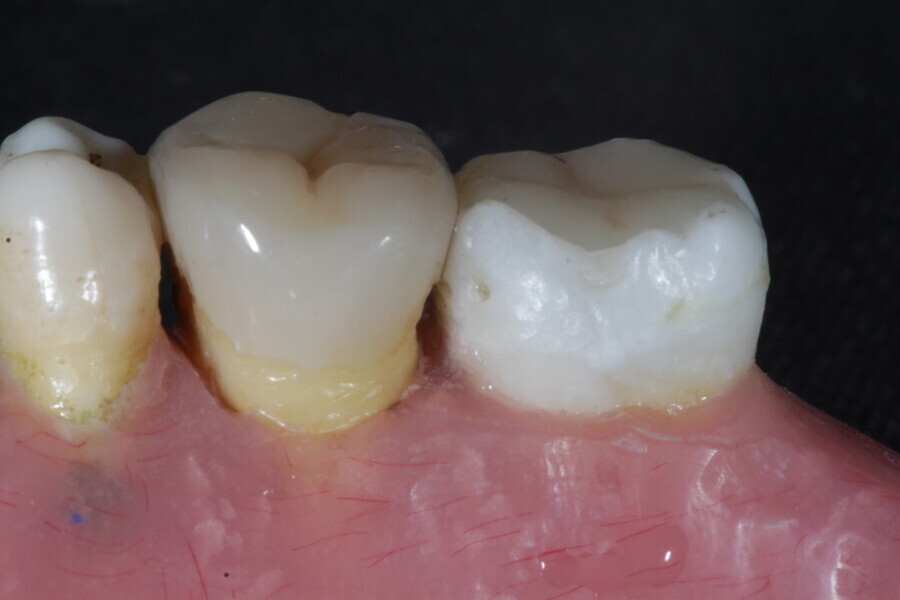

1. functional and aesthetic reconstruction of a maxillary anterior tooth using fibre-reinforced flexible micro-posts after endodontic treatment (Figs. 3–20);

Example 1—showing functional and aesthetic reconstruction of a maxillary anterior tooth using fibre-reinforced flexible micro-posts after endodontic treatment.

1. direct restoration using a fibre-reinforced flowable composite and membrane cube after endodontic treatment (Figs. 21–35); and

1. restoration reinforcement of a vital tooth with a fibre-reinforced flowable composite and membrane (Figs. 36–45).

Example 3—Restoration reinforcement of a vital tooth with a fibre-reinforced flowable composite and membrane.